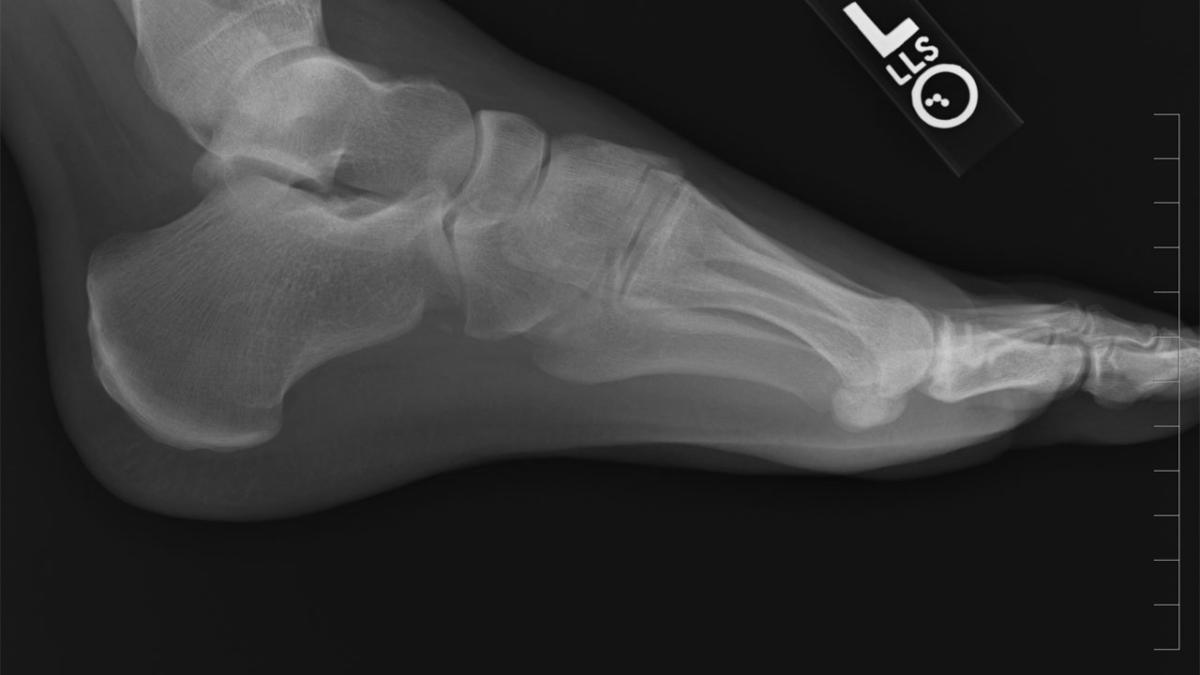

Думала, что просто растянула — но снимок показал другое: история, от которой мурашки

Стрессовые переломы стопы возникают у спортсменов из-за перегрузки при тренировках — врач Лиза Каллахан

Переломы усталости — это микротрещины в костной ткани, возникающие из-за чрезмерной нагрузки. На первый взгляд может показаться, что кость "сломалась сама по себе", ведь падений или ударов не было. Однако организм просто не успел восстановиться после слишком интенсивных тренировок.

Чаще всего страдают стопы и голени, ведь именно они принимают на себя основной удар при беге и прыжках. Боль может быть ноющей, усиливаться к вечеру или при ходьбе. Иногда отёк появляется позже, когда повреждение уже значительное.

Альтернатива: консультация ортопеда и диагностика с помощью рентгена или МРТ.